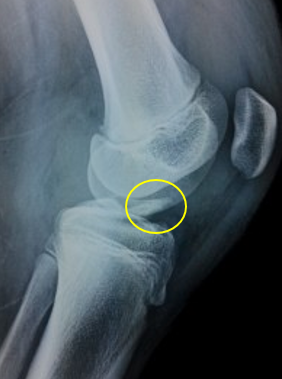

胫骨髁间嵴骨折

前交叉韧带损伤在儿童和青少年中越来越常见,损伤主要表现为两种形式:韧带实质部损伤和胫骨髁间棘撕脱骨折,团队经过20年的努力,已经将诊断及治疗流程标准化,目前正在科室行政主任杨征带领下承担北京市卫健委迎冬奥国际合作择优资助基金项目:中国儿童青少年前交叉韧带实质部损伤和胫骨髁间棘撕脱骨折诊疗指南的编写工作。